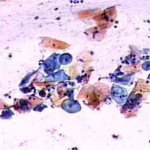

Πινακοθήκη κυτταρολογικών ευρημάτων ΙΙΙ

Οι πινακοθήκες κυτταρολογικών ευρημάτων, έχουν σαν στόχο να εμπλουτίσουν την κυτταρολογική εμπειρία σπουδαστών και ειδικευομένων, όπως ένας άτλαντας.

Παρουησιάζονται λοιπόν τυχαία ευρήματα, από το καθημερινό γυναικολογικό ιατρείο.